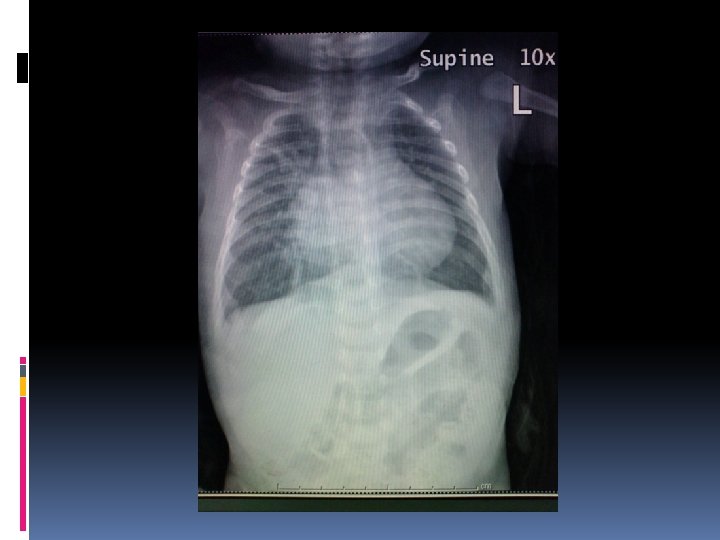

Case discussion: case I A male premature baby, birth weight 2. 1 kg Respiratory distress with heart murmur No dysmorphic feature Normal S 1, S 2 with SEM gr 2/6 at LPSB

Investigation Echocardiography Single functioning morphologic RV, DIRV, DORV, rudimentary LV, large bulboventricular foramen Mild MS, No AS, No PS hypoplastic aortic arch 3 mm, severe Co. A 2. 5 mm, PDA 3. 3 mm CTA heart

Operation and findings Severe coarctation of the aorta and hypoplastic aortic arch Hypoplastic LV Deep hypothermia + circulatory arrest Resection and end-to-end anastomosis Pulmonary artery banding